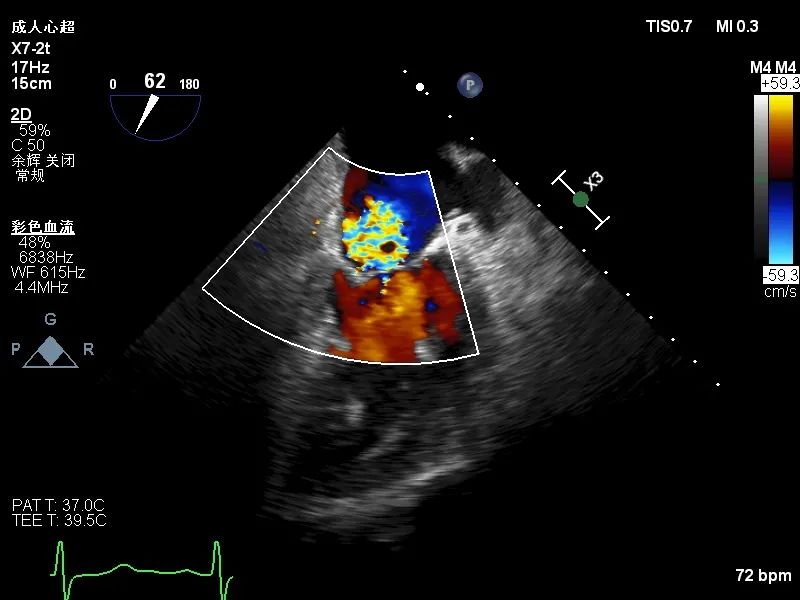

术后超声心动图

患者在麻醉科团队保驾护航下,器械经股静脉穿刺房间隔,通过输送系统送入左心房,到达二尖瓣瓣膜反流处,在经食道超声心动图及DSA引导下,术者通过反复评估二尖瓣膜脱垂范围、抓捕位置、反流程度之后,进行精准夹合,成功植入DragonFly瓣膜夹1枚。术后超声即刻患者反流降低至轻度,二尖瓣跨瓣平均压差未超过4mmHg,左房压下降,肺静脉逆流减轻,血流动力学改善明显,手术取得圆满成功。